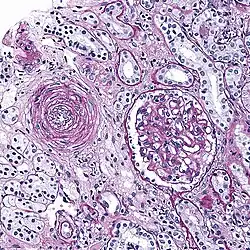

Hyaline arteriolosclerosis

Also arterial hyalinosis and arteriolar hyalinosis refers to thickening of the walls of arterioles by the deposits that appear as homogeneous pink hyaline material in routine staining.[3] It is a type of arteriolosclerosis, which refers to thickening of the arteriolar wall and is part of the aging process.[4]

This is a type of arteriolosclerosis involving a narrowed lumen.[4] The term "onion-skin" is sometimes used to describe this form of blood vessel[14] with thickened concentric smooth muscle cell layer and thickened, duplicated basement membrane. In malignant hypertension these hyperplastic changes are often accompanied by fibrinoid necrosis of the arterial intima and media. These changes are most prominent in the kidney and can lead to ischemia and acute kidney failure. In the brain, a small cavity called a lacune is an ischemic cavity that can arise due to brain necrosis, due to arteriolosclerosis.[15][16]